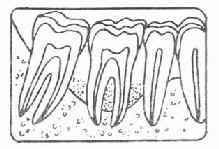

牙周袋形成:由于炎症的扩展,牙周膜被破坏,牙槽骨逐渐吸收,牙龈与牙根分离,使龈沟加深而形成牙周袋。可用探针测牙周袋深度。X线检查时可发现牙槽骨有不同程度的吸收。如图3-7~11.

| 图3-7 正常牙槽骨 | 图3-8 牙槽骨Ⅰ度吸收 |